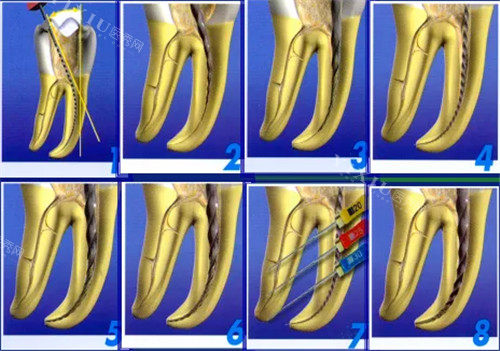

根管治疗

对于牙髓炎和根尖周炎等引起的牙痛和下颚疼痛,根管治疗是一种有效的治疗方法。

根管治疗通过清除受感染的牙髓组织,填充根管并封闭冠部,从而消除炎症、降低疼痛。根管治疗后,牙齿可能会变得脆弱,需要佩戴牙冠进行保护。